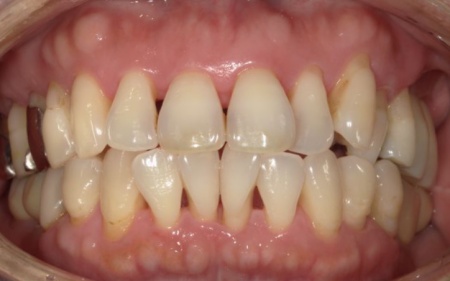

50代女性 温存が難しい奥歯を抜いてインプラントで噛み合わせを回復した症例

「他院で左上の親知らずを抜いたが、かなり腫れ、隣接する歯もグラグラするようになった。他院の説明では納得ができなかったため、セカンドオピニオンとしてこちらを受診した」とご相談いただきました。

カウンセリング・診断結果

拝見したところ、左上の抜歯部周辺は歯を支える骨が溶ける「骨吸収」が進行し、隣接している歯を含めた複数の歯がひどくグラグラしており、温存が困難です。

噛み合わせも安定していなかったため、このままでは残っている歯への負担が増加し、歯の揺れやさらなる噛み合わせの悪化につながるリスクがあります。